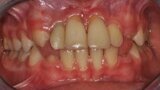

Ryc. 1_Stan miejscowy przed ekstrakcja zębów 11 i 21.